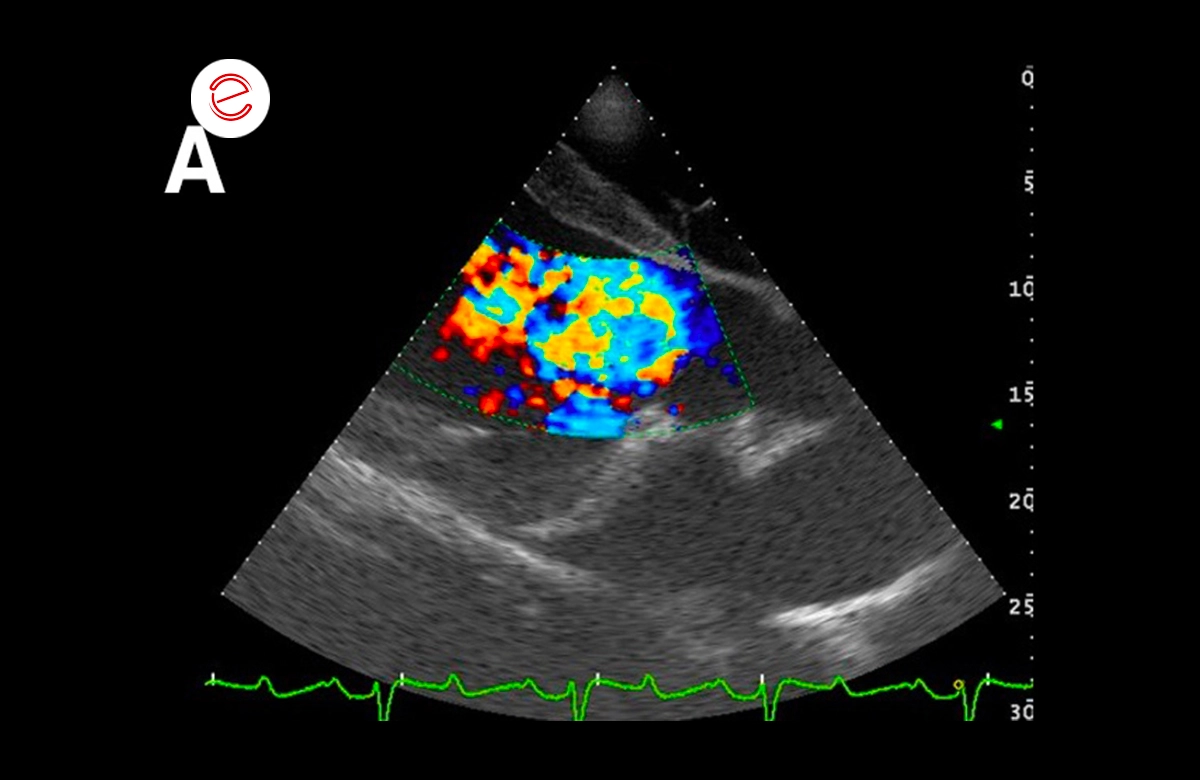

These images show: A) severe aortic regurgitation jet, B) severe mitral regurgitation jet; C) mild pulmonary regurgitation jet.